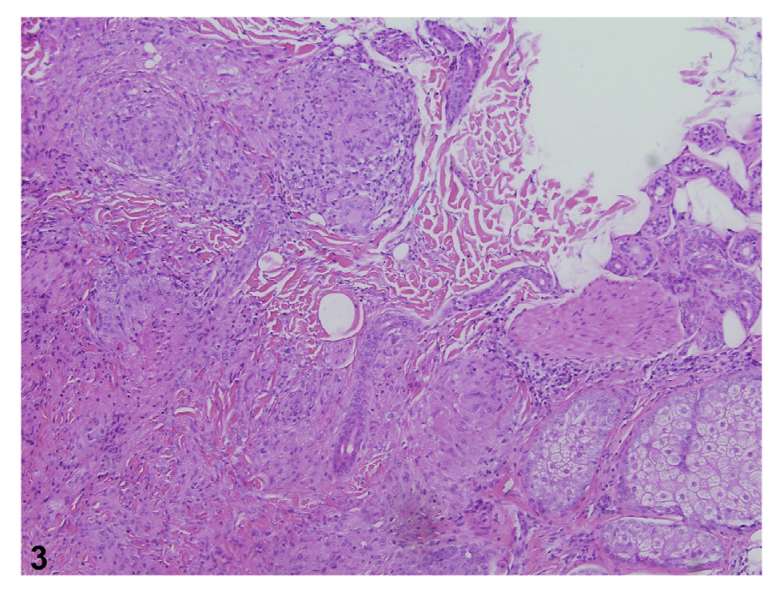

Biopsies of scalp sarcoid will show the classic pattern of inflammation that characterizes this disease: sarcoidal granulomas in the dermis. The key to the diagnosis is the characteristic noncaseating epitheloid granulomas. The central area has lymphocytes, macrophages, multinucleate giant cells and the is all surrounded by CD8 and CD4 positive T cells (and fibrosis).

Histopathology from a 43 year old patient with scalp sarcoidosis. The image shows typical ‘naked’ epithelioid granulomas with Langans type giant cells. There are no adnexal structures here suggesting this is a scarring alopecia. Image from Ghosh A et al. Single lesion of sarcoidosis presenting as cicatricial alopecia: a rare report from India. Int J Trichology . 2014 Apr;6(2):63-6. Image used with creative commons license.

Punch biopsy showing scalp sarcoidosis. Magnified views are shown below. Image from House NS et al. Sarcoidosis-induced alopecia.Dermatol Online J 2012 Aug 15;18(8):4. Image used and shown with creative commons license.

Punch biopsy showing scalp sarcoidosis. Naked granulomas with epithelioid histiocytes and Langhans type giant cells are seen. Image from House NS et al. Sarcoidosis-induced alopecia.Dermatol Online J 2012 Aug 15;18(8):4. Image used and shown with creative commons license.

Histology of scalp in patient with sarcoidosis showing non-caseating granulomas. Image from Barker C et al. Scarring alopecia and scalp pruritus. JAAD Case Rep. 2022 Nov 2;30:134-136. doi: 10.1016/j.jdcr.2022.10.021. eCollection 2022 Dec. Image used with creative commons license.